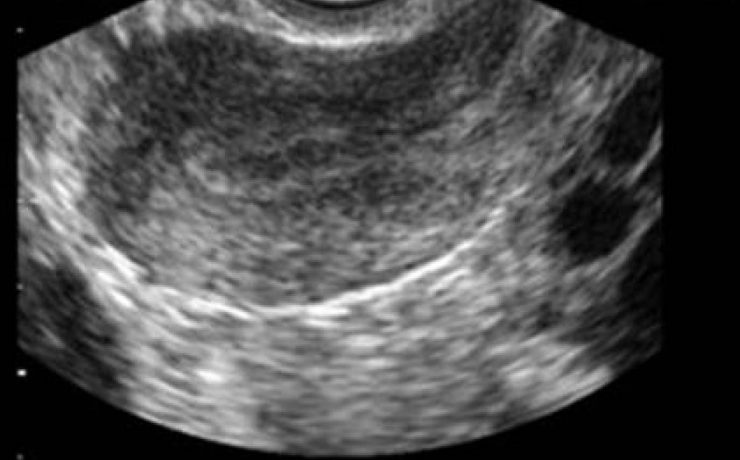

La incidencia de coledocolitiasis después de la intervención quirúrgica tiene una incidencia del 10 porciento, Los cálculos pueden permanecer por años dentro de la vía extra hepática y no manifestar síntomas. Los cálculos pequeños pueden pasar por el colédoco y el duodeno sin producir síntomas (menores 3mm), solo que se